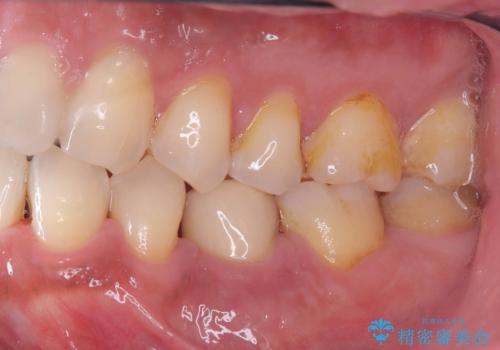

インプラントは虫歯にはなりませんが、しっかりケアをしないと歯周病にはなってしまいます。

歯周病は歯の病気ではなく、骨の病気なので歯やインプラントは骨に支えられているため進行すると揺れてきてしまいます。

なので、衛生士による定期的なクリーニングはとても大事です。